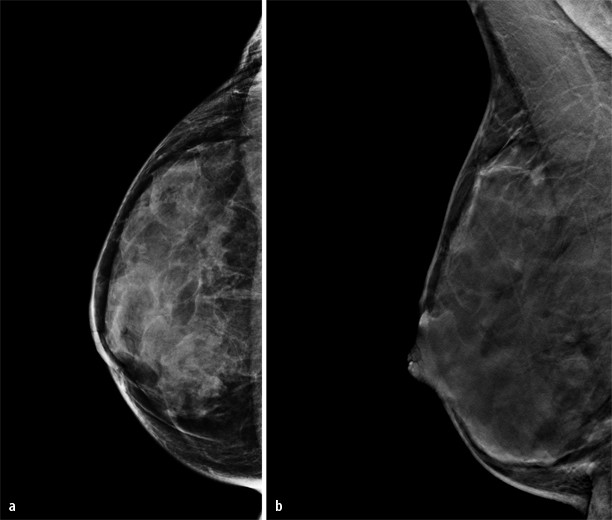

Es handelt sich dabei um neu gebildetes Bindegewebe der Brust das die Milchdrüsenläppchen umgibt. Wird ein gutartiger Tumor in der Brust entdeckt erfolgt die weitere Diagnose meist mittels Sonographie oder auch Mammographie. Krankheit weibliche brust - gutartiger tumor stock-grafiken -clipart -cartoons und -symbole entfernung von gutartigen tumoren im kosmetik-salon.

Fibroadenome in der Brust entstehen aus Drüsen- und Bindegewebe und treten überwiegend bei jüngeren Frauen auf. Der häufigste gutartige Tumor der Brust das Fibroadenom kommt vor allem bei jüngeren Frauen vor. Bei älteren Frauen findet man hingegen öfter eine so genannte Mastopathie das heisst eine diffuse knotige Veränderung die manchmal beidseits zu zahlreichen Verhärtungen in der Brust führt.

Über 80 neue Produkte zum Festpreis. Der häufigste gutartige Tumor der Brust ist das sogenannte Fibroadenom. Knapp ein Drittel aller Frauen vor allem auch jüngere sind davon betroffen.